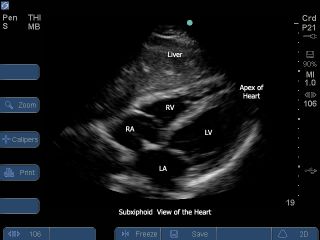

But I digress. I feel strongly that we ought to have a simple echo (like a sono-site; there is a great subcostal view to the right here) available at EVERY code, and the team ought to be trained to get the

windows that tell you what you need to know to diagnose the mechanical causes of PEA. It’s time. There are no disposables, so it’s a one-time cost. If you are being fussy about sterility, a sandwich bag with a tie-wrap, or a transderm-type occlusive sticky will do. I suppose you could have the ultrasonography team respond to every code as an alternative. But that seems like overkill, and in any case, crowds the room. It's time to do the (inevitable) validation work with and without. After all, an artist is only as good as his tools...